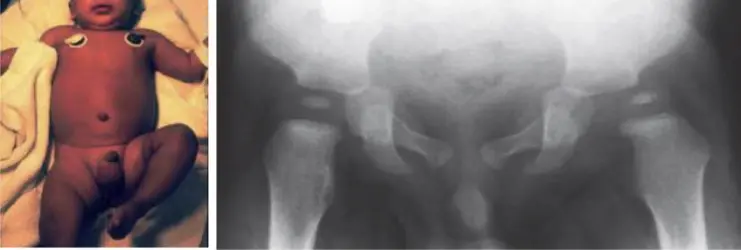

DDH

| DDH Risk Factors (“3 Fs” + others) | * Antenatal: Illnesses/complications during pregnancy, oligohydramnios. |

| * Birth History: Delivery complications, breech presentation (especially frank), APGAR score, C-section vs. vaginal, multiple birth, NICU admission. | |

| * Post-natal: Ever in Pavlik Harness or hip spica cast? | |

| * Family History: DDH or other hip problems? | |

| Neonatal Examination for Developmental Dysplasia of the Hip (DDH) - Ortolani Test / Barlow Test (NOT PART OF OSCE) | Ortolani Test Purpose: Reduces a dislocated hip. Expected finding: Feel a “clunk” (not a “click”). Barlow Test Purpose: Dislocates a reduced hip. Expected finding: Feel a “clunk” (not a “click”). | Ortolani Test technique Purpose: Reduces a dislocated hip - Expected finding: Feel a “clunk” (not a “click”) ![]() Barlow Test technique Purpose: Dislocates a reduced hip - Expected finding: Feel a “clunk” (not a “click”) ![]() Combined Ortolani/Barlow technique ![]() ![]() | |